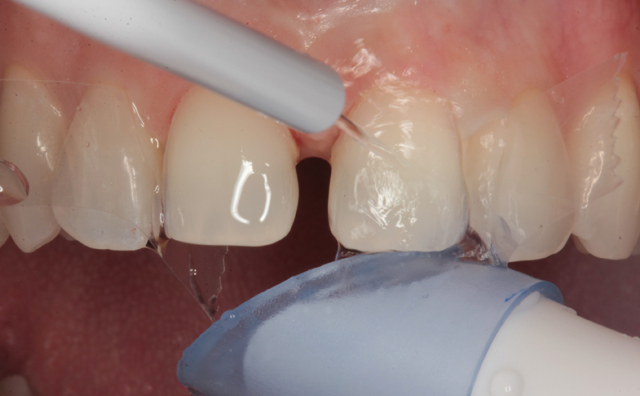

At the delivery appointment, the provisional veneers were removed and the new laminate veneers were tried in using Calibra try in paste (Dentsply/Sirona). The patient was asked to look in a mirror and she approved the new veneers. The veneers were removed and thoroughly cleaned with water spray from an air/water syringe and dried with oil-free air. A silane primer (Calibra Silane Coupling Agent, Dentsply/Sirona) was used to treat the etched intaglio surfaces (Fig. 9), allowed to dwell for twenty seconds and air dried.

Fig. 9 Fig. 10

Celluloid strips were placed distal to both central incisors to protect the adjacent teeth. Phosphoric acid edging gel (Calibra, Dentsply/Sirona) was placed on the prepared enamel surfaces (Fig. 10), thoroughly rinsed after ten seconds (Fig. 11) and air dried (Fig. 12).